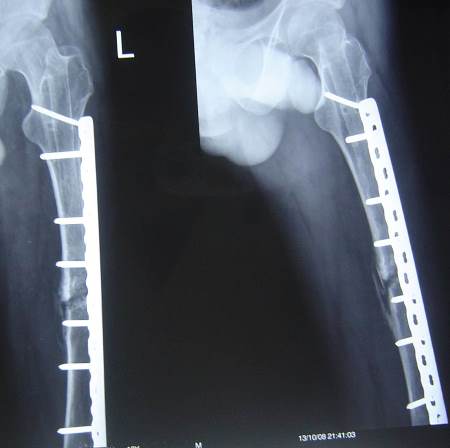

19-year-old male had fracture of femur which was treated by open IM nailing with aseptic non-union for 2 years where stiff knee arthroscopy and knee manipulation were done.

A few months later the patient presented with 2 nail breaks.

Perioperative data:

• Operative time: 4 hours nail removal + 2 hours plate insertion.

• Blood loss: 2000cc, 3 units transfused.

• Middle part of the nail was removed by a small break in the lateral cortex.

• Distal part of the nail was removed by a hole distally in the lateral cortex then pushed by a drill pit and pulled through the medulla by an intestinal clamp.

• Bone graft.

• No infection postoperative.